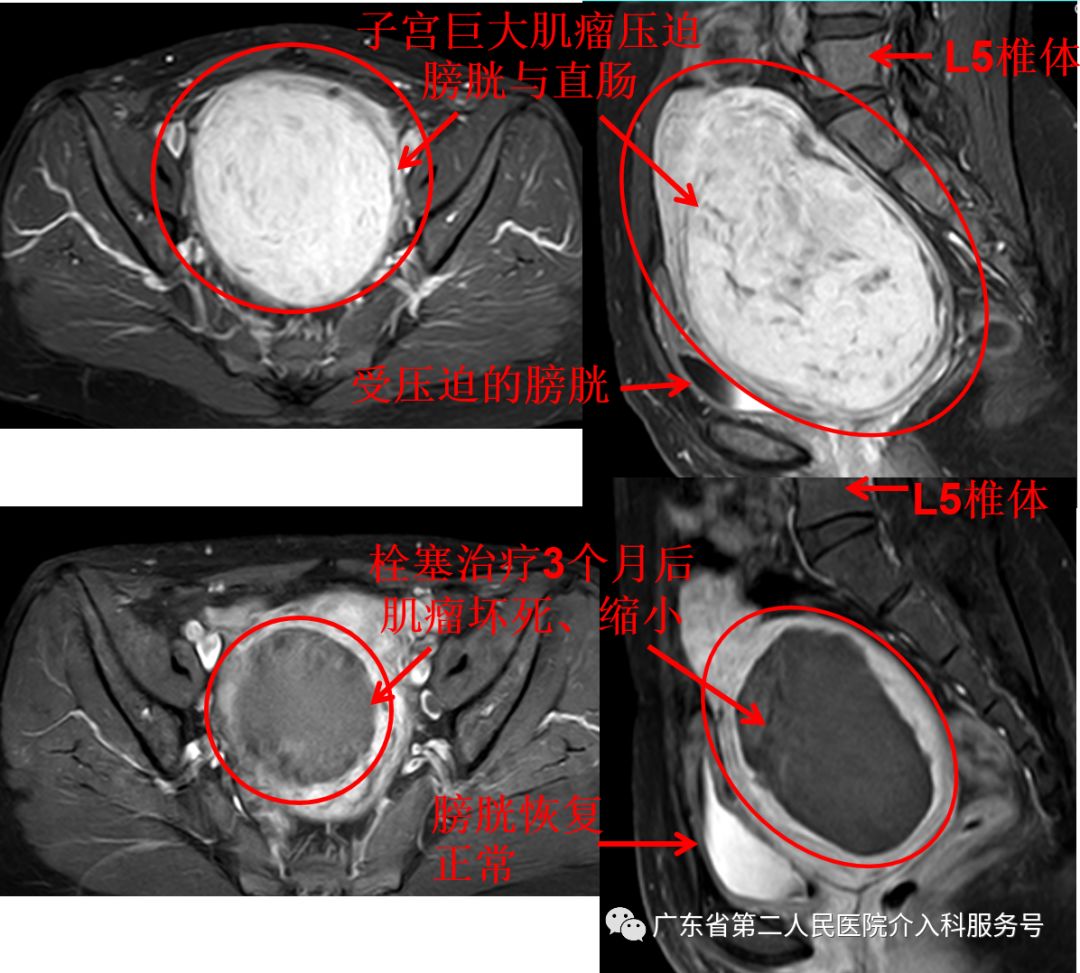

下图为王女士的子宫肌瘤血供丰富(肌瘤血液供应充足,生长旺盛),微创栓塞治疗后子宫肌瘤血供消失(肌瘤缺乏生长的血液后则坏死、吸收、缩小)。

治疗后差不多1个月,王女士的“大姨妈”驾到,量正常,第6天即干净,再也没有淋沥不净的尴尬。3个月后,王女士例假依然正常,已没有贫血貌,现在久坐后站立时再也没有出现眼前发黑(黑蒙)的现象,腹部平坦,大小便正常。王女士高兴的说:终于摆脱“大姨妈”来时排山倒海,淋沥不净的烦恼,关键是可以和其他女性一样保留子宫,正常来月经,没有血块,不会淋沥不净,生活也舒坦了。门诊复查血红蛋白在正常范围,磁共振如下(子宫肌瘤已坏死、吸收、缩小(8cm*7cm*5cm),随后还是的肌瘤还会继续吸收、缩小)。